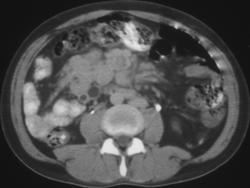

Gastric Leiomyosarcoma (w/ IVC Clot)